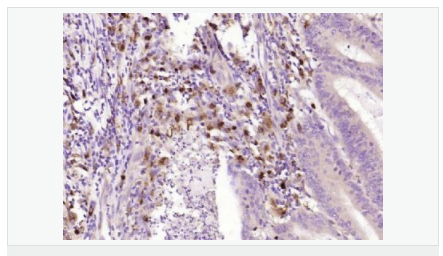

| 產(chǎn)品應(yīng)用 | WB=1:500-2000 ELISA=1:5000-10000 IHC-P=1:100-500 IHC-F=1:100-500 ICC=1:100-500 IF=1:100-500 (石蠟切片需做抗原修復) not yet tested in other applications. optimal dilutions/concentrations should be determined by the end user. |

| 產(chǎn)品介紹 | This gene encodes an aldo-keto reductase that catalyzes the NADPH-dependent reduction of pteridine derivatives and is important in the biosynthesis of tetrahydrobiopterin (BH4). Mutations in this gene result in DOPA-responsive dystonia due to sepiaterin reductase deficiency. A pseudogene has been identified on chromosome 1. [provided by RefSeq, Jul 2008] Function: Catalyzes the final one or two reductions in tetra-hydrobiopterin biosynthesis to form 5,6,7,8-tetrahydrobiopterin. Subunit: Homodimer. Subcellular Location: Cytoplasm. Post-translational modifications: In vitro phosphorylation of Ser-213 by CaMK2 does not change kinetic parameters. DISEASE: Defects in SPR are the cause of dystonia DOPA-responsive due to sepiapterin reductase deficiency (DRDSPRD) [MIM:612716]. In the majority of cases, patients manifest progressive psychomotor retardation, dystonia and spasticity. Cognitive anomalies are also often present. The disease is due to severe dopamine and serotonin deficiencies in the central nervous system caused by a defect in BH4 synthesis. Dystonia is defined by the presence of sustained involuntary muscle contractions, often leading to abnormal postures. Similarity: Belongs to the sepiapterin reductase family. SWISS: P35270 Gene ID: 6697 Database links: Entrez Gene: 6697 Human Omim: 182125 Human SwissProt: P35270 Human Unigene: 301540 Human Important Note: This product as supplied is intended for research use only, not for use in human, therapeutic or diagnostic applications. |